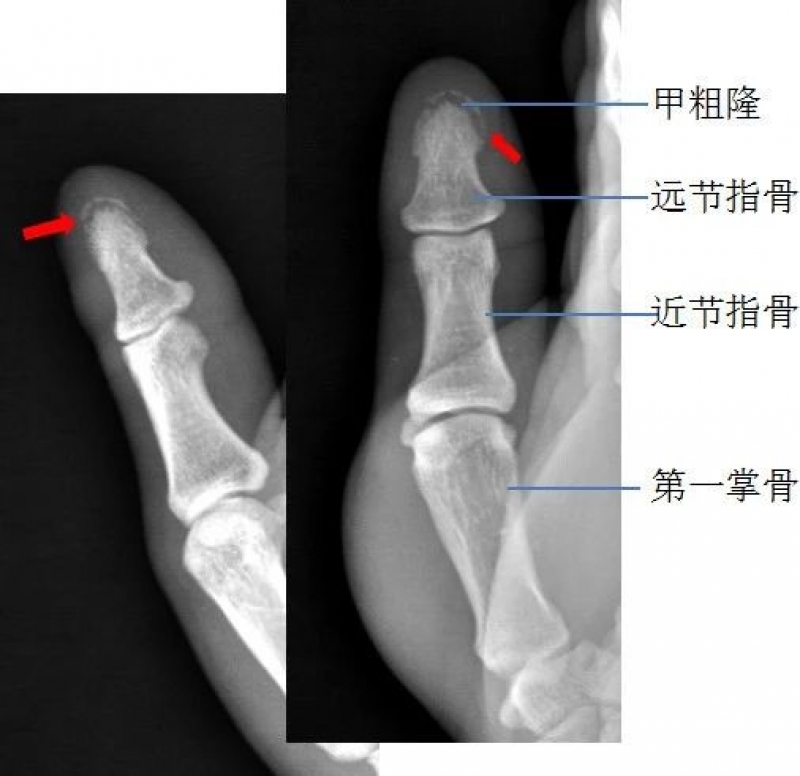

右手拇指远节指骨甲粗隆游离骨碎片影

右手拇指末节指骨见数条骨折线,骨折端对位对线尚可右手拇指末节指骨粉碎性骨折